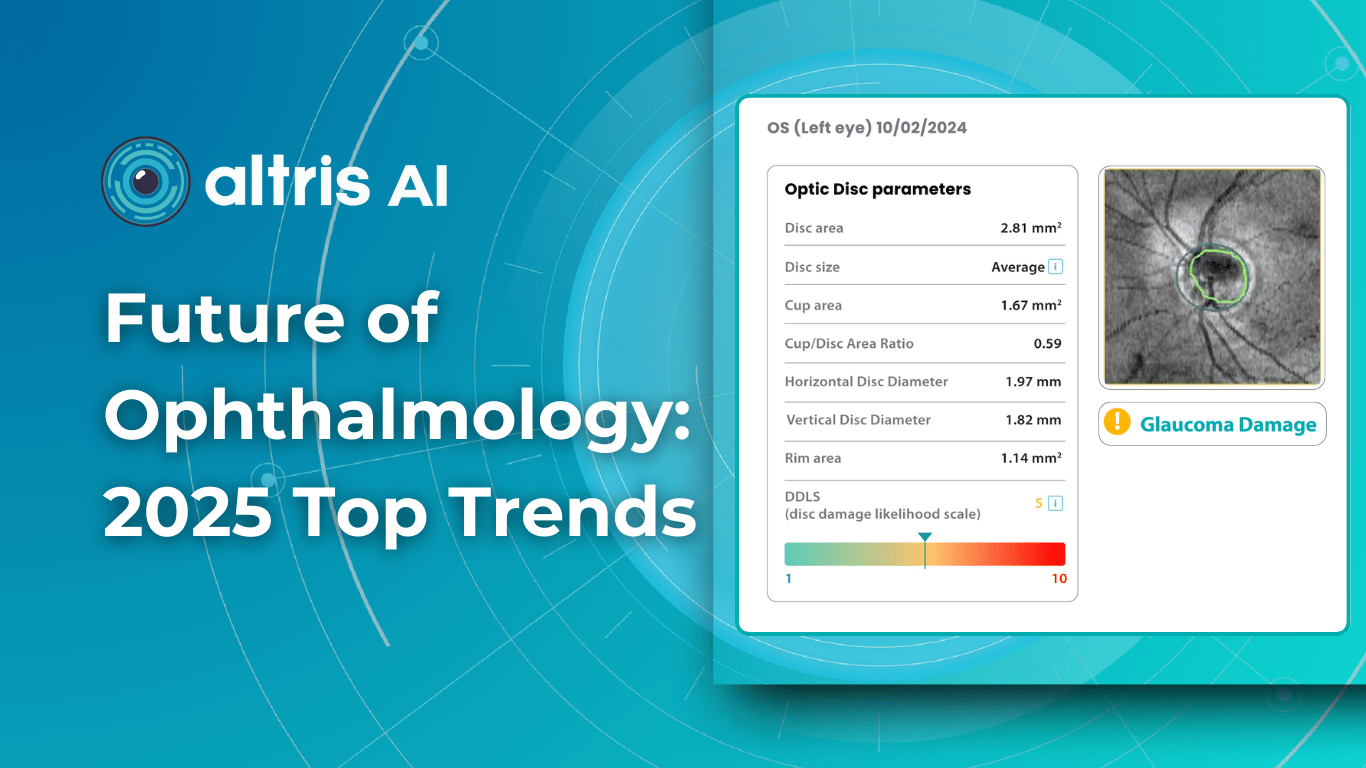

For this article, we surveyed eye care professionals on which optometry technology appears most promising to them. The answers were divided among AI for more precise diagnostics, advanced contact lenses, and new iterations of OCTs.

New tech in optometry: AI for Medical Image Analysis

AI has blossomed in recent years, transforming not only how we work and relax but also how we manage our health. It’s no surprise that our survey of professionals revealed AI as the most promising technology in optometry.

The most immediate and practical AI implementation in optometry is the analysis of medical images, such as fundus photos and OCT scans.

For instance, AI today can assess the early risk of glaucoma based on the GCC asymmetry measurements. Here is how AI-powered OCT workflow would look.

AI-assisted readings of OCT scans are already helping not only with pathology detection but also with the analysis of its progression or response to treatment. This represents a new approach to monitoring, where practitioners no longer need to sift through various patient notes but can directly compare reports from previous examinations and observe how, for instance, shadowing has changed in micrometers.

AI programs are becoming even more invaluable with an aging population, as diseases prevalent in older individuals become increasingly common while ophthalmology and optometry face a shortage of specialists. This situation will transform the optometrist’s role, with AI empowering practitioners with the diagnostic capabilities to manage many conditions without referral. This will benefit patients, enabling timely routine screenings and diagnoses and preventing months-long waits that can sometimes lead to irreversible blindness.